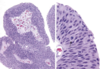

What are the KEY features on this H and E taken from a kidney tumor? Tumor Type?

•uniform round cells with abundant, intensely eosinophilic and granular cytoplasm = MITOCHONDRIA

***NOTABLY no PLEOMORPHISM***

•uniform small, round and central nuclei, Evenly dispersed chromatin

What is shown here?

• key features?

Oncocytoma

Key Features:

- Oncocytic = pink and grainy with sheets of pink and grainy PINK cells

- UNIFORM, not much pleomorphism

- smooth cell borders